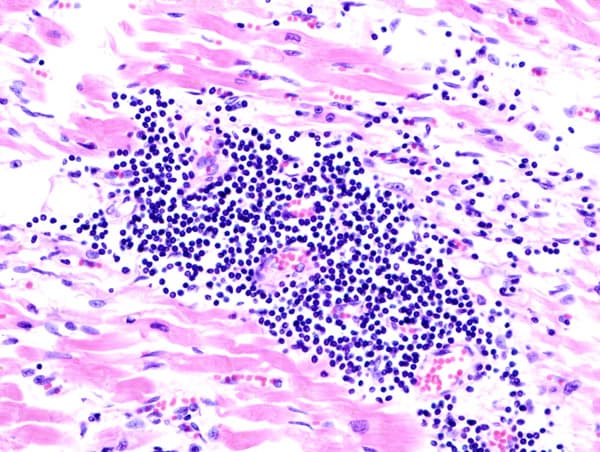

La myocardite est une atteinte inflammatoire du myocarde de causes variées. Les artères coronaires sont saines contrairement à une cause ischémique. La maladie peut être asymptomatique jusqu'à son terme, qu'elle évolue spontanément vers une issue favorable (guérison) ou non (risque de mort subite). Lorsqu'elle est symptomatique, elle peut se manifester de diverses manières : douleur thoracique, parfois de type péricarditique, prolongée et inhibant la respiration. La présence d'un frottement péricarditique à l'auscultation cardiaque est inconstante mais assez évocatrice ; fièvre, notamment dans les cas d'infection ; palpitations, tachycardie (pouls rapide) ; hypotension artérielle ; syncopes ; insuffisance cardiaque : dyspnée (essoufflement), œdème des membres inférieurs, œdème aigu du poumon ; syndrome pseudo-grippal notamment après une infection virale : symptômes ORL, fatigue, céphalées ; Si elle est grave, la détérioration du fonctionnement cardiaque peut être à l'origine d'une mort subite causée par des troubles du rythme cardiaque ou d'une insuffisance cardiaque. On parle de myocardite aiguë face à une insuffisance cardiaque récente, sans maladie coronarienne ni valvulaire évolutive. La myocardite est dite fulminante si les premiers signes cliniques apparaissent très vite (en quelques jours) après une crise pseudo-grippale (souvent alors induite par un virus à tropisme cardiaque comme le Parvovirus B19 le virus herpès de type 6, les Coxsackies et les adénovirus). Le risque d'une dégradation de la santé avec défaillances viscérales voire arrêt cardiaque implique une prise en charge dans un établissement disposant d’assistance cardiaque. Des formes plus progressives et subaiguës demandent un traitement conventionnel pour insuffisance cardiaque et parfois immunosuppresseur ou immunomodulateur (selon l'étiologie de la myocardite). Prise de sang : La prise de sang montre une inflammation (élévation de la CRP et de la VS) et une augmentation des marqueurs cardiaques (troponine et CK).